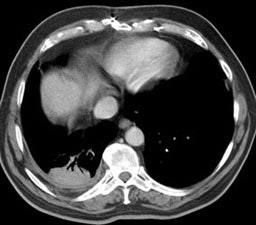

Computed Tomography: On CT the pleural thickening or calcification is clearly identified. Thickened lung markings and vessels swirl into the lesion which abuts the pleural surface ("comet tail sign"- central bronchovascular pedicle)- however, this finding may be absent in up to 8% of cases. Curvilinear air bronchograms are often visible within round atelectasis. The lesion is very commonly based or tethered by a strand to a thickened pleural surface. Pericicatril emphysema may also be seen. Volume loss within the affected lung is also common- often characterized by displacement of the fissure bounding the affected lobe. Calcification may also be found within areas of round atelectasis (up to 25% of cases)- possibly secondary to engulfment of a granuloma within the atelectatic lung, or invagination of a calcified pleural plaque. The lesion will enhance homogeneously after the administration of I.V. contrast (up to nearly 90% of cases). Inhomogeneous enhancement is atypical for rounded atelectasis [12].

Round atelectasis on PET FDG imaging: The images below demonstrate the typical CT and FDG PET findings in round atelectasis. On CT, there are thickened lung markings and vessels which swirl into the lesion that abuts an area of pleural thickening. Note the lack of metabolic activity in round atelectasis on PET imaging. |